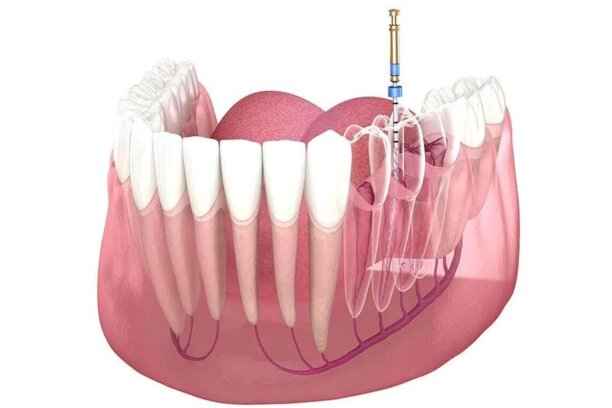

6. حشو عصب الأسنان (الحشو الجذري)

عندما يصل التسوس إلى العصب، يصبح حشو العصب ضرورة حتمية للحفاظ على السن. يهدف هذا الإجراء إلى:

- إزالة العصب الملتهب أو التالف بالكامل.

- تعقيم قنوات الجذر بدقة عالية.

- منع انتشار العدوى إلى العظم المحيط.

- الحفاظ على السن بدلًا من خلعه.

- استعادة الوظيفة الطبيعية للسن بعد الترميم.

حشو عصب الأسنان

يُعتبر حشو العصب من الإجراءات الدقيقة التي تتطلب خبرة عالية وأدوات متقدمة. الهدف منه إنقاذ السن ومنع فقدانه. فوائد هذا الإجراء تشمل:

- القضاء على الألم الحاد الناتج عن التهاب العصب.

- إيقاف انتشار العدوى.

- الحفاظ على بنية السن الطبيعية.

- إمكانية ترميم السن لاحقًا بتاج أو حشوة مناسبة.

- استعادة القدرة على المضغ دون ألم.

عملية حشو عصب الأسنان

تمر عملية حشو العصب بعدة مراحل منظمة لضمان النجاح الكامل. تشمل هذه المراحل:

- تشخيص دقيق باستخدام الأشعة.

- تخدير موضعي مريح.

- فتح السن للوصول إلى قنوات الجذر.

- تنظيف وتعقيم القنوات بعناية.

- حشو القنوات بمواد مخصصة.

- إغلاق السن وترميمه بحشوة أو تاج مناسب.

متى يتم اللجوء إلى حشو عصب الأسنان؟

يتم اللجوء إلى حشو عصب الأسنان في الحالات التالية:

- ألم شديد ومستمر عند تناول الطعام الساخن أو البارد أو التعرض للهواء البارد، مما يشير إلى التهاب العصب.

- وجود تسوس عميق تجاوز المينا والعاج، حيث لا يكفي الحشو التقليدي.

- ظهور خراج أو تورم في اللثة نتيجة عدوى وصلت إلى جذر السن.

- تصدع أو كسر يصل إلى العصب، ما يهدد السن بالعدوى وفقدان بنيته الداخلية.

- الحاجة لتحضير السن لتركيب تاج أو جسر بعد إزالة التسوس أو التحضير لترميم أكبر.

- حشو العصب (الحشو الجذري): يعالج الالتهابات العميقة ويحمي السن من الخلع ويعيد استقراره.

- حشو العصب (الحشو الجذري): ينظف ويعقم القنوات الجذرية ويحمي السن من العدوى.

- حشو العصب: يعتمد على جودة العملية والمتابعة، وقد يدوم أكثر من 10 سنوات.

سعر حشو العصب في السعودية

تتراوح سعر حشو العصب في السعودية بحسب عدد قنوات الجذر وتعقيد الحالة:

- عادة يبدأ السعر من 800 ريال سعودي للسن ذي قناة واحدة.

- قد يصل إلى 1500 ريال سعودي للأسنان الخلفية ذات أكثر من قناة.

- في بعض الحالات المعقدة، يمكن أن يشمل العلاج متابعة إضافية وتركيب حشوة دائمة أو تاج، ويظل ضمن باقات عروض حشو اسنان المتوفرة في مركز أضواء الحكمة.